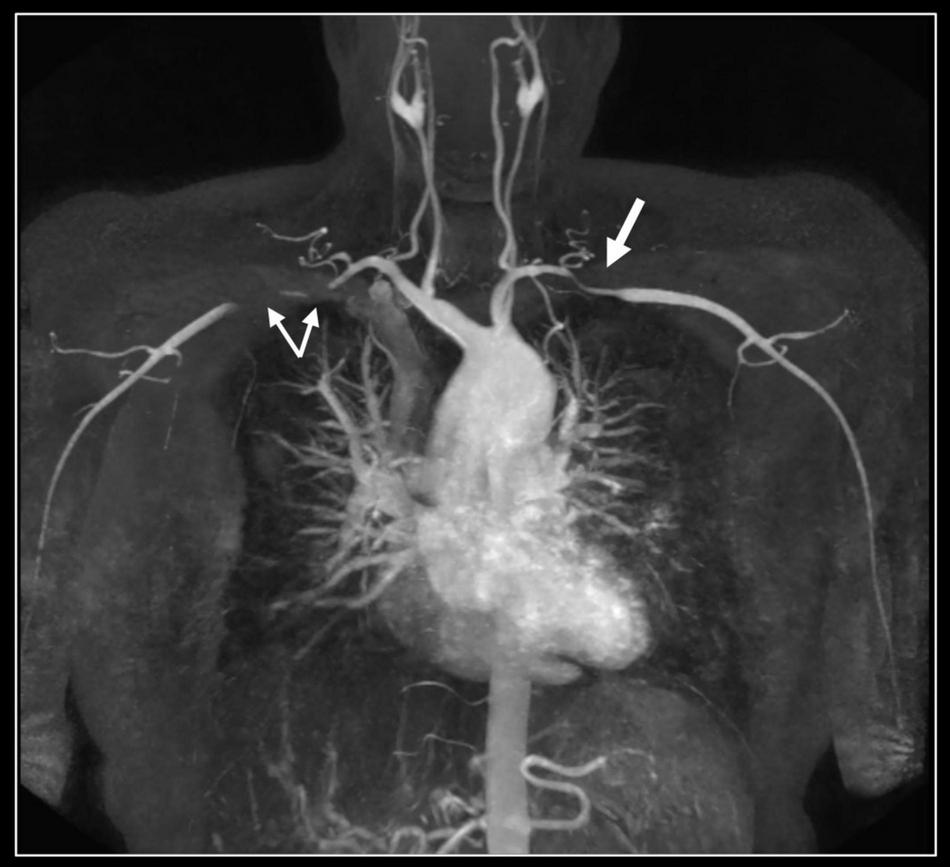

FIGURE 4

Contrast-enhanced 3D MR angiography. Forty-year-old woman known with Takayasu disease treated with steroids and immunosuppressive therapy (Imuran). At coronal MIP a focal high-grade narrowing of the right subclavian (thin arrows) and less severe stenosis of the left subclavian coronary artery (thick arrow) can be well appreciated. No evidence of aneurysm formation of the thoracic aorta (ascending aorta 32 mm) nor of the side branches.